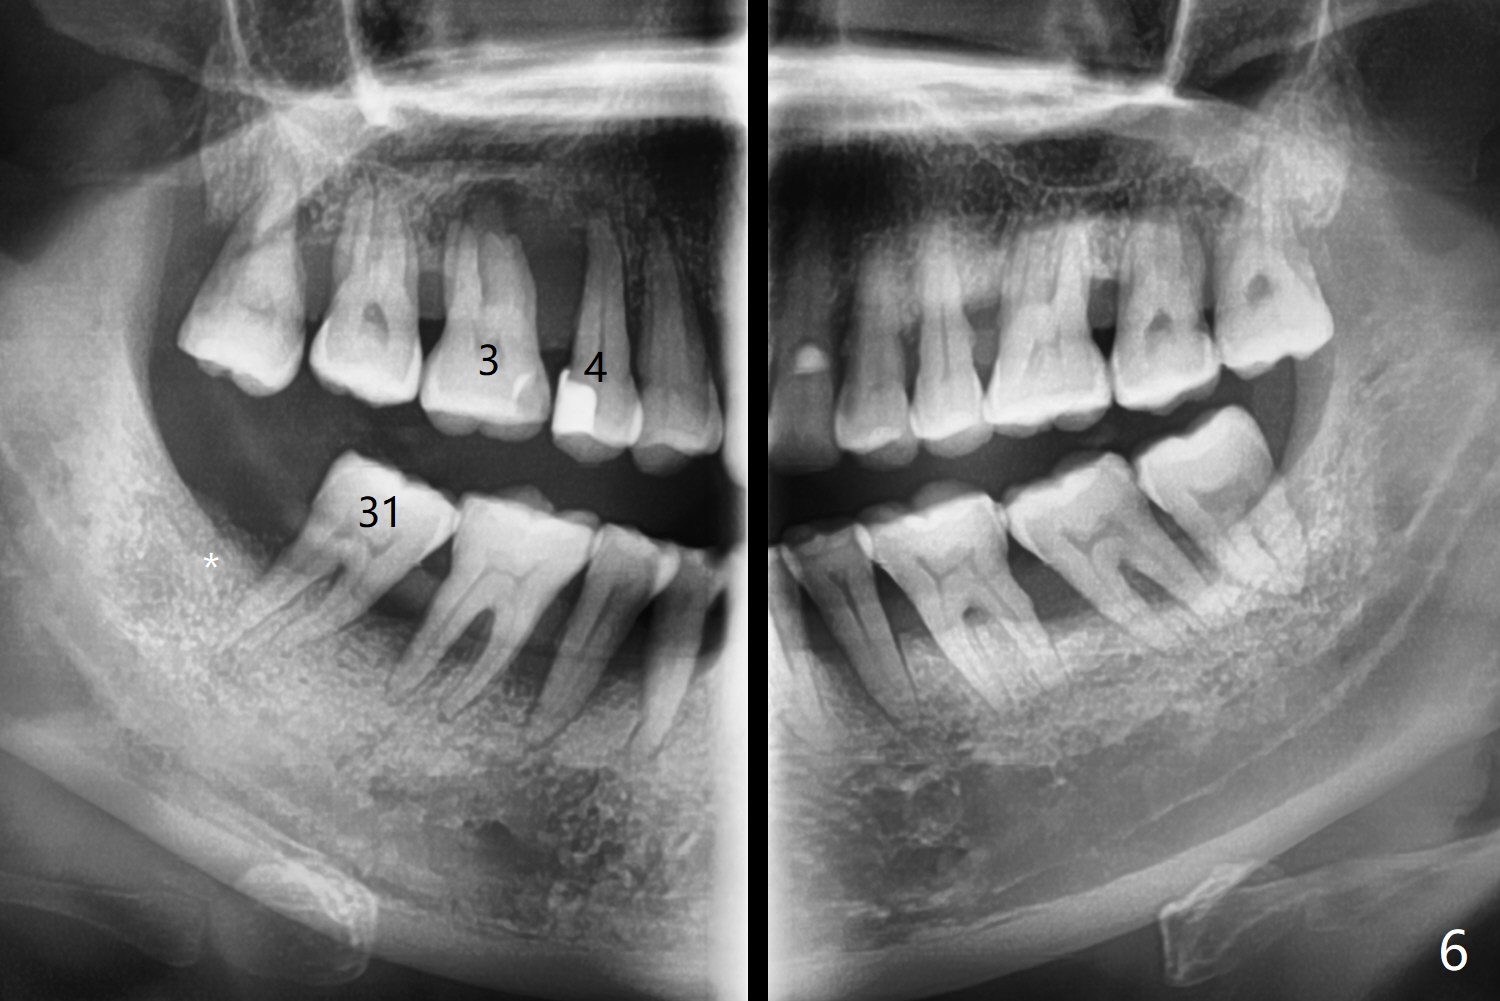

with Severe Bone Loss

A 44-year-old woman (YHM) has generalized moderate localized severe chronic periodontitis (Fig.1). Periodontal abscess develops between the teeth #31 and 32. Since the pain and mobility is more severe at #32 than 31, the former is extracted (Fig.2). After thorough curettage and copious irrigation, Osteogen plug is placed in the distal portion of the socket (Fig.3, 4 O), while allograft in the mesial one (B), with collagen plug on the top (C) before suturing (Fig.5). The tooth #31 is stable and pain-free with formation of new bone distal 7 months postop (Fig.6,6' *), while bone loss at #3 and 4 is more severe.